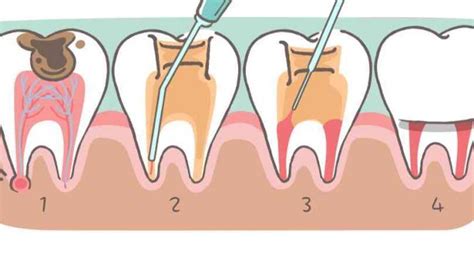

Dantų šaknų kanalų gydymo etapai: 1. Diagnostika ir planavimas. 2. Mechaninis ir cheminis kanalų paruošimas. 3. Kanalų užpildymas. 4. Danties atstatymas.

Kiek svarbu laiku reaguoti? Jei jausdami pirminius simptomus, atidėliosime vizitą pas gydytoją odontologą, progresuojantis kariesas gali pažeisti danties nervą, bakterijos pateks į pulpą ir sukels „nervo uždegimą” (pulpitą), o vėliau ir periodontitą. Odontologas po vietinės nejautros, pašalina nervą, išvalo danties kanalus, užpildo juos plombavimo medžiaga ir uždeda plombą. Krūminių dantų atveju po endodontinio gydymo, rekomenduojamas danties protezavimas.

Tokiais atvejais reikalinga endodontinė terapija, žinoma kaip šaknų kanalų gydymas. Šios procedūros metu odontologas pašalina pažeistą ar užkrėstą pulpą iš šaknies kanalo, tada kruopščiai išvalo kanalo vidų ir užpildo jį specialia medžiaga, kad būtų išvengta tolimesnės infekcijos. Ši procedūra pašalina skausmą, o dantis išlieka išsaugotas, nors nebėra gyvybiškai svarbus, nes nėra nervo. Dantų šaknų kanalų gydymas yra veiksmingas būdas išsaugoti dantis net ir esant stipriai infekcijai, yra populiari alternatyva dantų šalinimui. Ši procedūra leidžia pacientams išlaikyti dantų funkcionalumą ir estetinę išvaizdą, o infekcija visiškai pašalinama.

Endodontinis gydymas - tai dantų šaknų kanalų gydymas. Šio gydymo eigoje itin dažnai naudojamas mikroskopas. Dėl šios priežasties odontologas itin dažnai siunčia pratęsti dantų gydymą pas endodontą, kadangi reikalinga tam tikra įranga bei specialios žinios dirbant su mikroskopu. Šaknų kanalų gydymas neatidėliotinas, kuomet danties šaknies kanale išsivystęs uždegimas paveikia ten esančią pulpą. Turbūt teko girdėti apie danties pulpą: kaip svarbu išlaikyti ją nepažeistą, greičiau išsigydant dantis, nes kitaip gydymas gali tapti itin komplikuotu. Pulpa - danties kanalo viršuje esantis kraujagyslių, nervų ir limfagyslių raizginys. Danties kanalo infekcija, uždegimas kyla neprižiūrint, negydant dantų, netaisant dantyje ar jo plomboje atsiradusių įtrūkimų, per kuriuos patekusios bakterijos tirpdo gadina dantį, prieidamos iki pat kanalo. Pakenkti danties pulpai gali net trauma - sumušimas, nors išoriškai dantis gali atrodyti nepažeistas. Negydant, ignoruojant danties kanalo infekciją, uždegimą, tik skatinsite abceso (pūlinio) atsiradimą. Endodontinio gydymo metu stengiamasi išsaugoti natūralų dantį, jeigu tik yra galimybė.